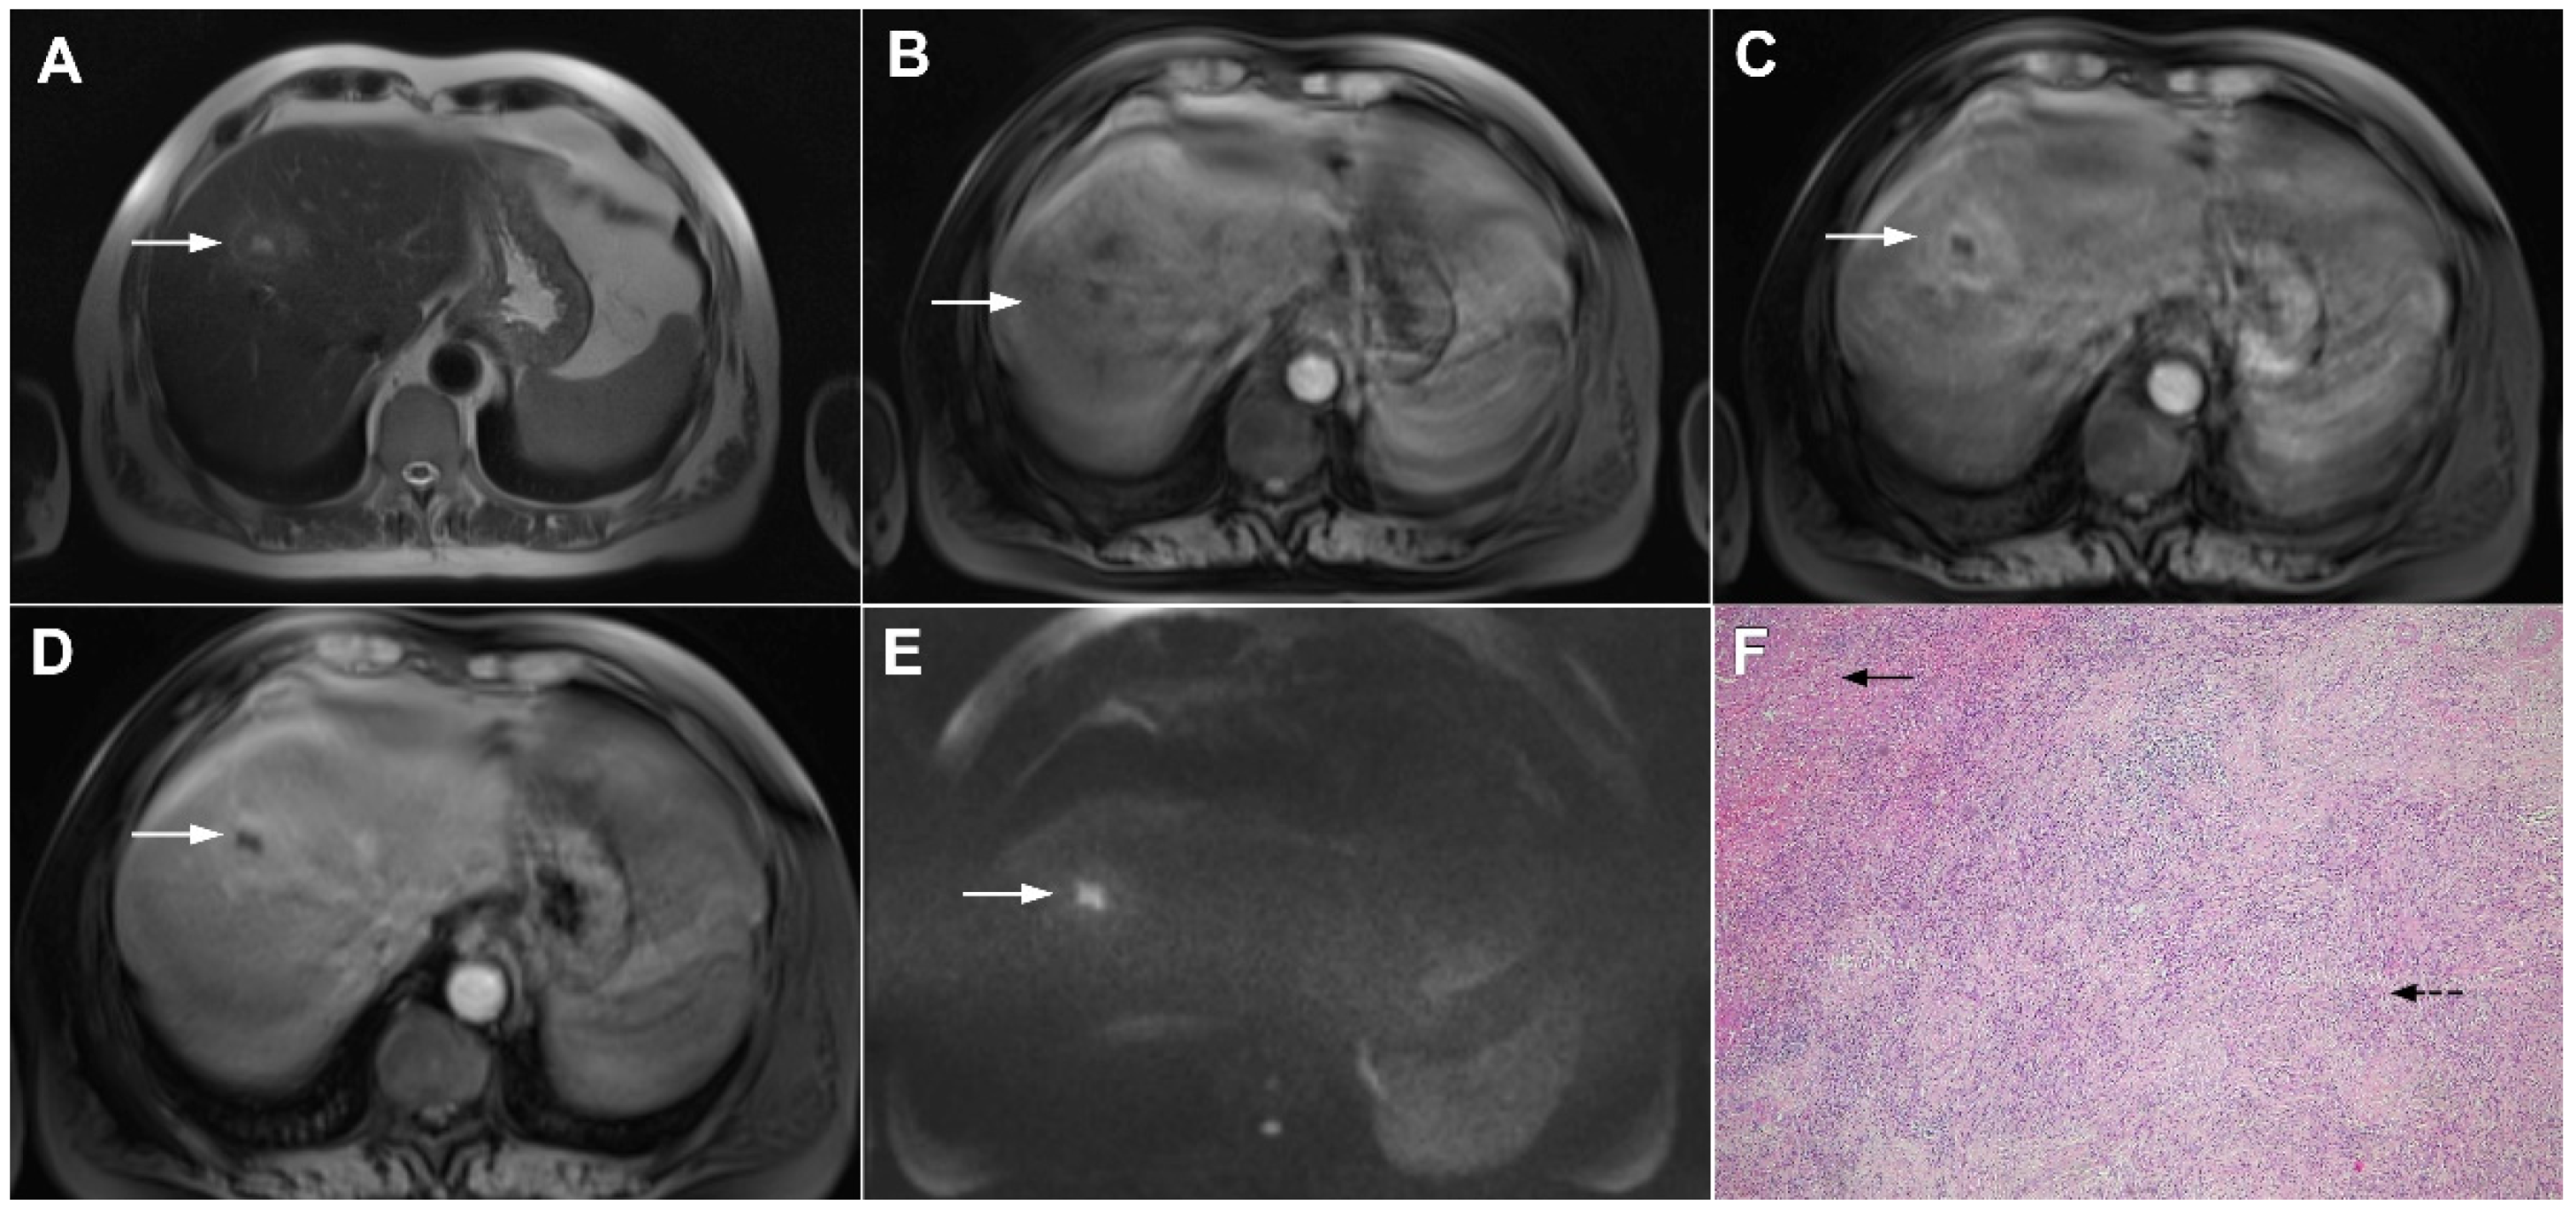

Figure 8.

Focal confluent fibrosis in a 42-year-old man with long-standing primary sclerosing cholangitis. The T2-weighted image (A) shows a band like a slightly hyperintense lesion (arrow) at the dome of the liver. On the plain T1-weighted image (B) the lesion (arrow) is hypointense without arterial vascularity (C) while homogeneous progressive enhancement is seen in the portal venous (D) and delayed phases (E). The lesion (arrow) shows high signal intensity in DWI (F).